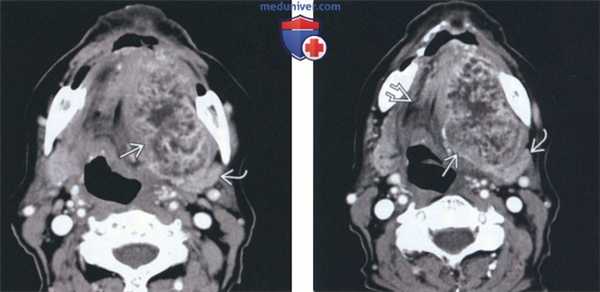

(Слева) На корональной КТ с КУ определяется асимметрия слизистой оболочки в области заднего края твердого неба. Определяется ремоделирование неба и большой небной борозды. Утолщение слизистой оболочки дна правой верхнечелюстной пазухи является случайной находкой, не связанной с изменениями неба.

(Справа) На аксиальной КТ с КУ в мягком небе определяется хорошо отграниченное, слегка неоднородное мягкотканное образование, минимально накапливающее контраст. При интраоперационном патоморфологическом исследовании подтвердилась доброкачественная смешанная опухоль (ДСО).

(Слева) На аксиальной МРТ (Т1 ВИ С+ FS) в области соединения твердого и мягкого неба слева определяется объемное образование с минимально неравномерным накоплением контраста. Контуры образования позволяют заподозрить злокачественную опухоль, но при интраоперационном морфологическом исследовании подтвердилась ДСО.

(Справа) На корональной МРТ (Т1 С+ F5) у этого же пациента определяется равномерное накопление контраста В Учтите, что лучевые признаки неспецифичны, хотя четкие контуры и гладкие участки ремоделирования кости могут свидетельствовать о доброкачественной опухоли или о низкой степени злокачественности. Была выполнена тотальная резекция, подтвердилась плеоморфная аденома.